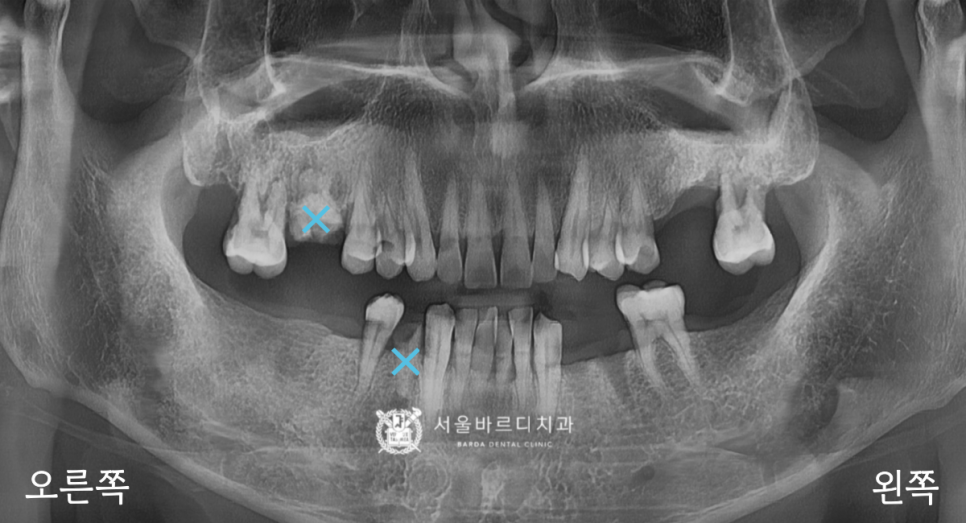

위와 같은 과정을 통해 보철을 모두 넣어드리고,

전반적으로 확인하기 위한 파노라마를 촬영했습니다.

위아래 높낮이에 잘 맞춰서 제작해 드린 덕분에

딱딱 부딪힐 때도 걸리는 부분이 없이

편안하다고 말씀하셨는데요.